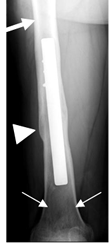

Fig 42. Fractura en osteoporosis.

Rx AP. Postquirúrgico de fractura del fémur. Disminución en la densidad

de la metáfisis distal (Flecha delgada). Cortical normal en el tercio proximal (Flecha gruesa) y engrosamiento de la cortical en la zona de consolidación de la fractura (Punta de flecha).